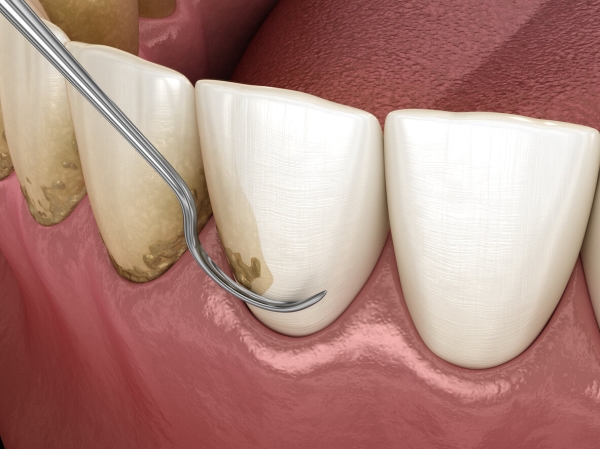

جرم گیری دندان با ابزارهای دستی

در این روش، دندانپزشک از ابزارهای فلزی به نام جرم گیر و کورت استفاده می کند تا جرم ها را از سطح دندان بتراشد. سر این ابزارها بسیار ظریف است و می تواند به زیر خط لثه نفوذ کند. در نتیجه پلاک های زیر لثه هم با استفاده از این ابزارها تراشیده خواهند شد.